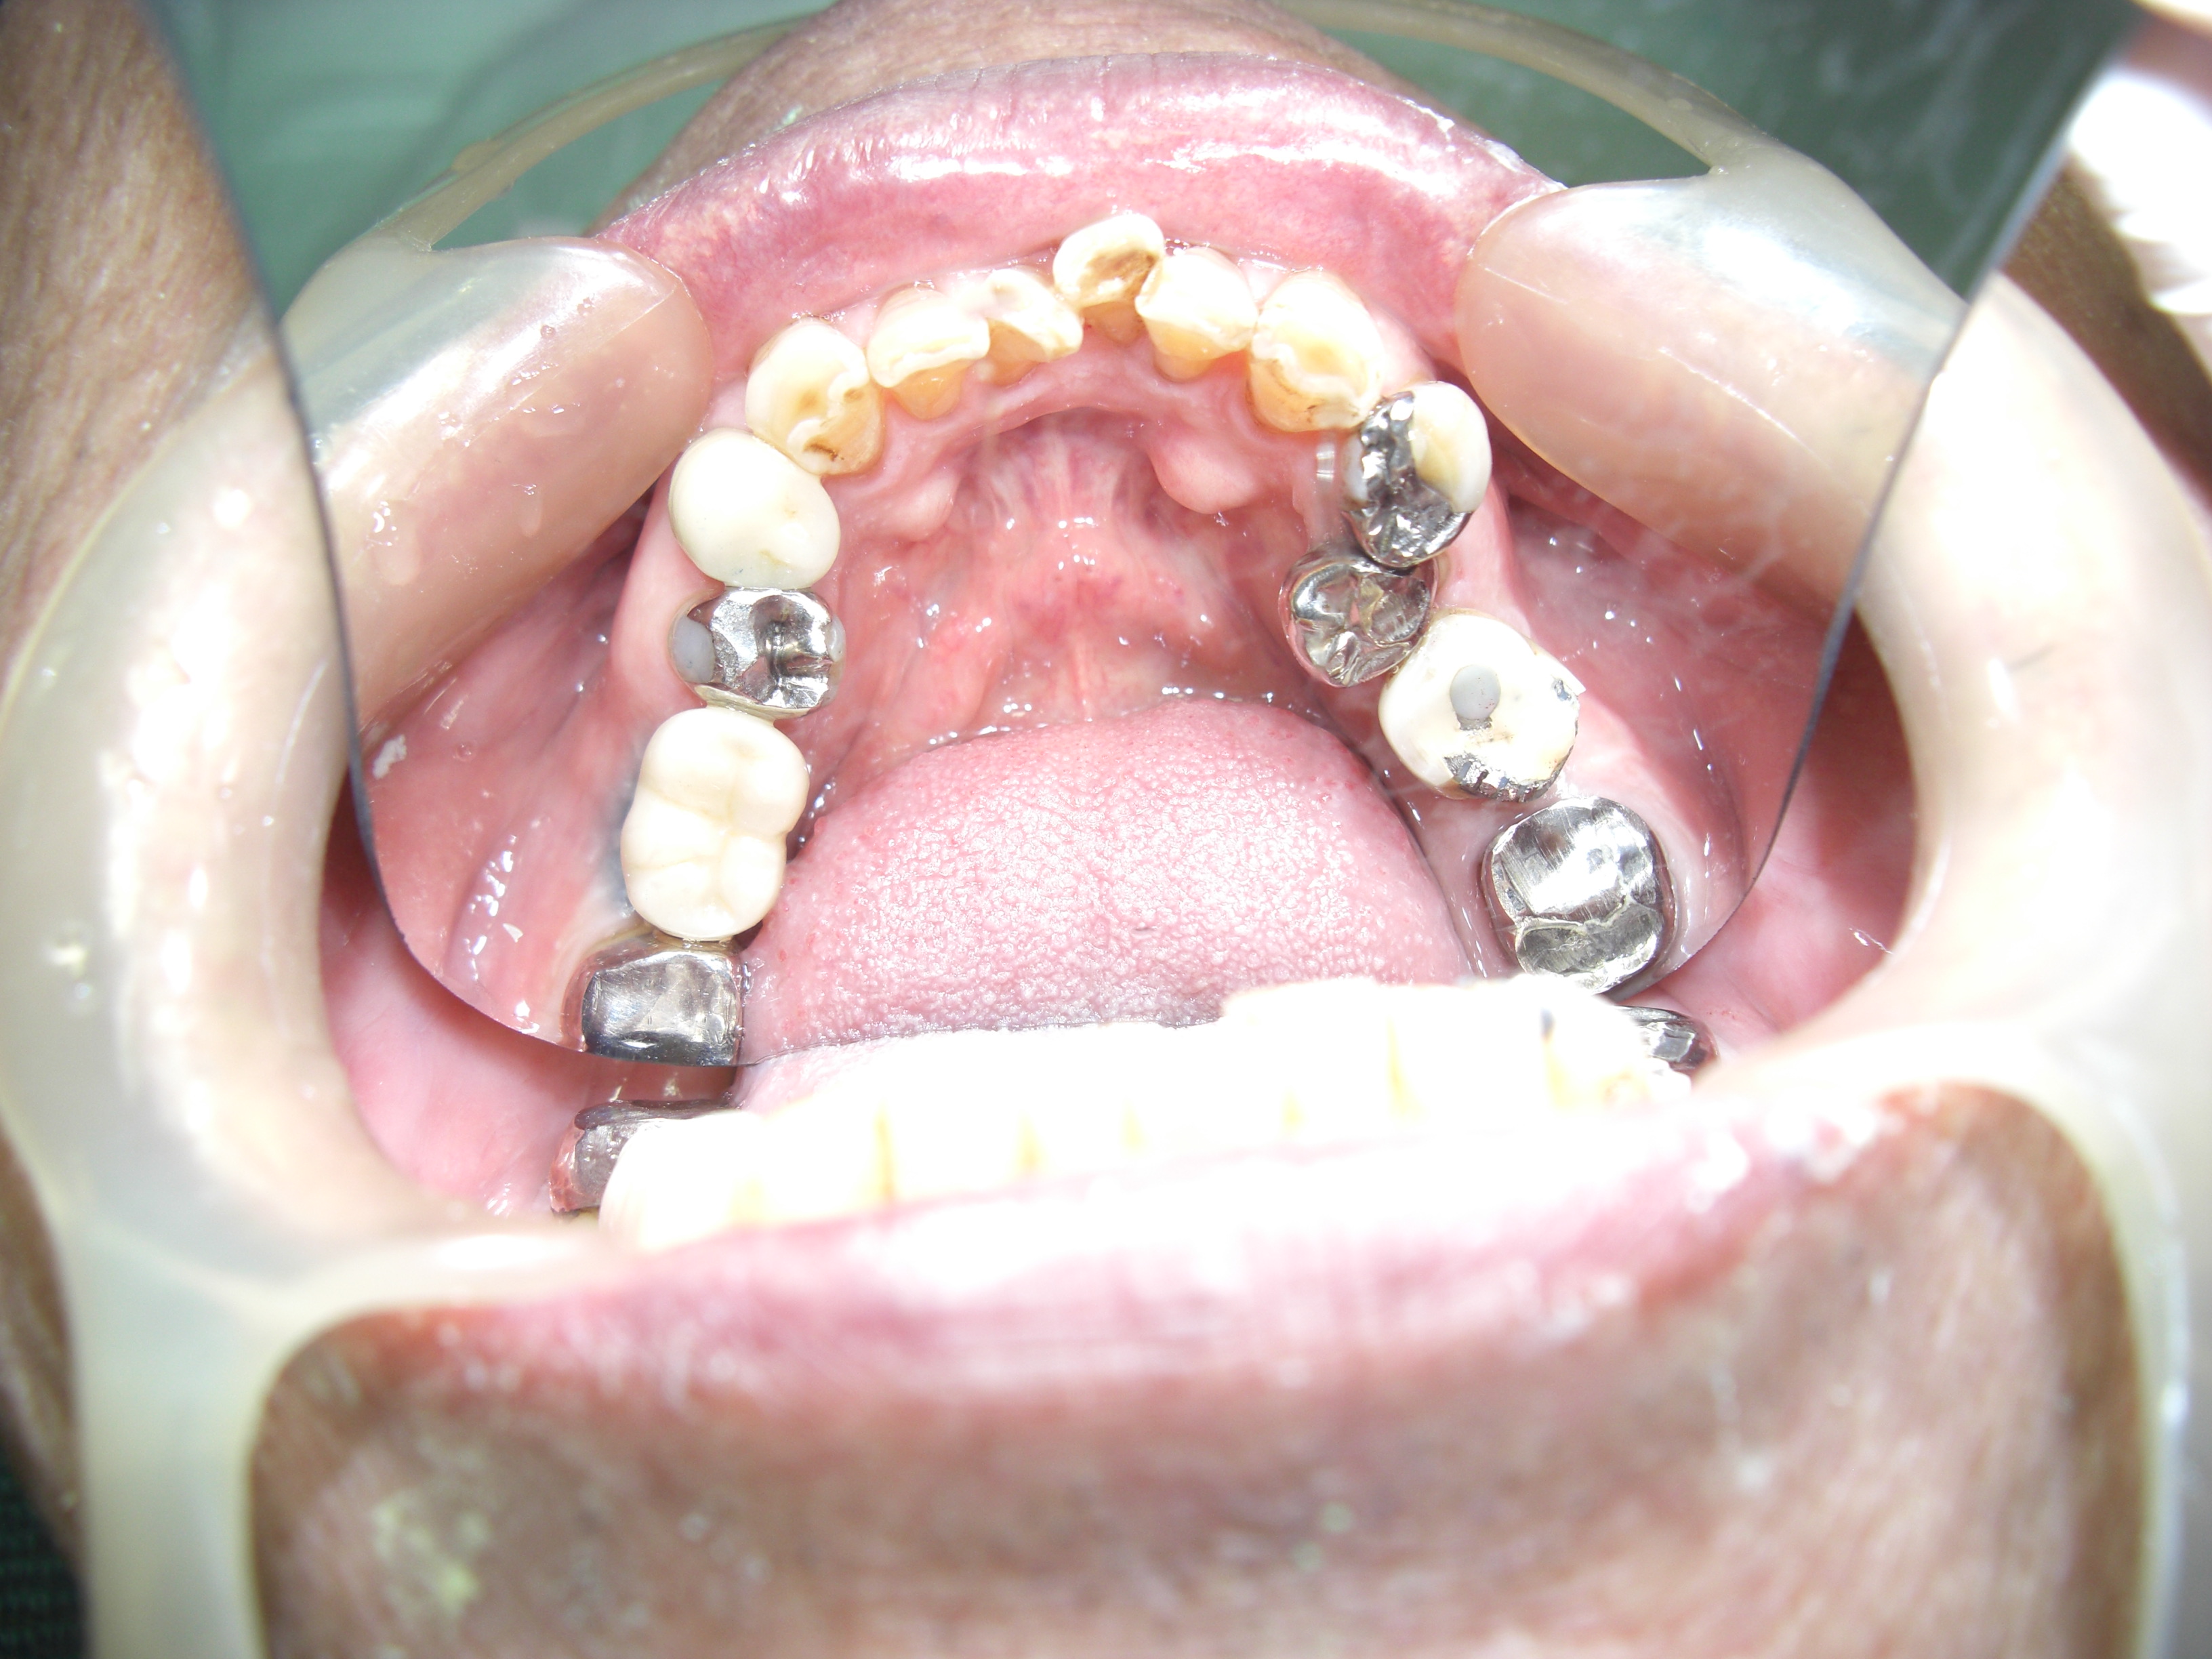

上顎の口腔内

5本新たにインプラントを追加しましたが

30年前にO歯科医院で行ったインプラントも

問題なくしっかりと使えています。